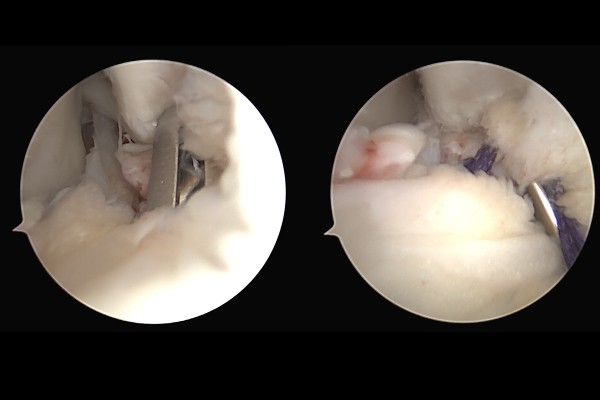

파열된 인대를 바늘과 같은 수술도구로 떠서 실을 통과시켜 묶어 줍니다.(실은 칼슘나사와 결합되어 있습니다.)